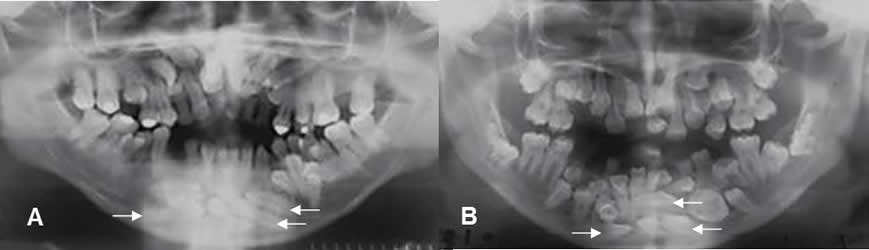

Fig 79. Dientes supernumerarios.

A y B: Ortopantografías. Gran cantidad de dientes supernumerarios, con predominio en la linea media de la mandíbula. Gran cantidad de piezas muestran alteración de su orientación, estando horizontalizadas.